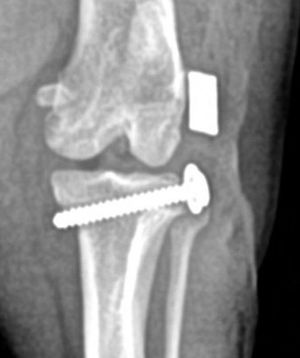

The washered-anchor techniqueByMark Besancon, DVM November 7th 2025A refinement of the lateral extracapsular repair.